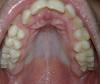

I'am Опубликовано 6 января, 2010 Автор Поделиться Опубликовано 6 января, 2010 верх Ссылка на комментарий

I'am Опубликовано 6 января, 2010 Автор Поделиться Опубликовано 6 января, 2010 http://radikal.ru/F/s55.radikal.ru/i149/10...5a6b84.jpg.html сомкнуты http://radikal.ru/F/s45.radikal.ru/i109/10...c7f2b3.jpg.html низ Ссылка на комментарий